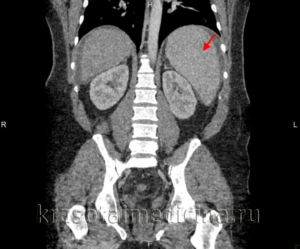

- Дополнительные методы исследования, включая ультразвуковое исследование, компьютерную и магнитно-резонансную томографию, диафаноскопию и другие, используемые в сочетании в зависимости от случая.

В случае подозрения на спленомегалию может быть назначено ультразвуковое исследование (ультразвук). Этот метод позволяет получить более детальную информацию о размерах и структуре селезенки, а также о наличии возможных опухолей или кист. Ультразвук также может помочь определить причину увеличения селезенки, такую как цирроз печени или инфекционные заболевания.